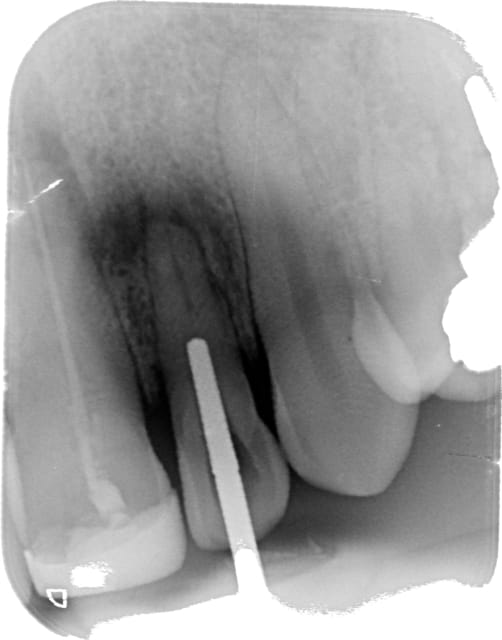

Patient sans ATCD.

Dent nécrosée depuis de nombreuses années. granulome étendu. 11 a retraiter aussi. puis résection apicale à envisager.

Ouverture camérale tendue. J'ai pris sur moi d'y aller.

Ça partait bien et puis le dernier coup de fraise flamme a fait la perfo.

Il aurait été mieux d'avoir un conebeam petit champ pour voir le canal.

Maintenant la perforation complique les chances de conservation de la dent sur l'arcade au vue de sa petite taille (rapport couronne/racine)

Je ne me lancerais pas dans une chir endo, vu la longueur très faible déjà de la racine, il ne te restera pas un rapport couronne/racine suffisant pour conserver la dent par la suite.

3 - Recupéré le canal qui certes est bas, mais bien visible à la RA